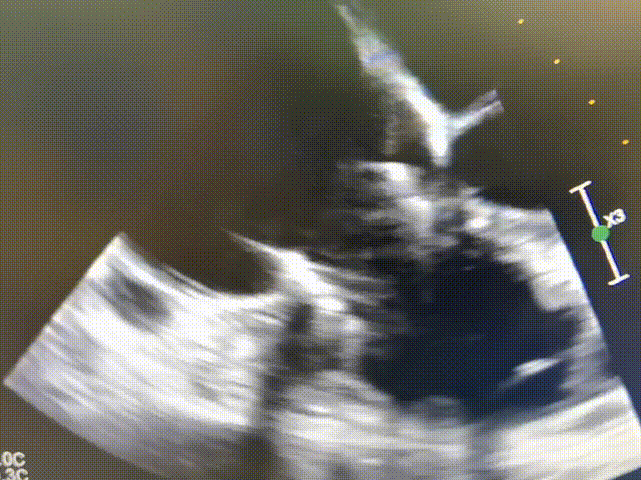

术前食道超声显示:三尖瓣成形术后表现,重度中心性三尖瓣反流,考虑右心室扩大牵拉三尖瓣腱索所致,瓣口面积4.0cm²。

术前三尖瓣重度反流